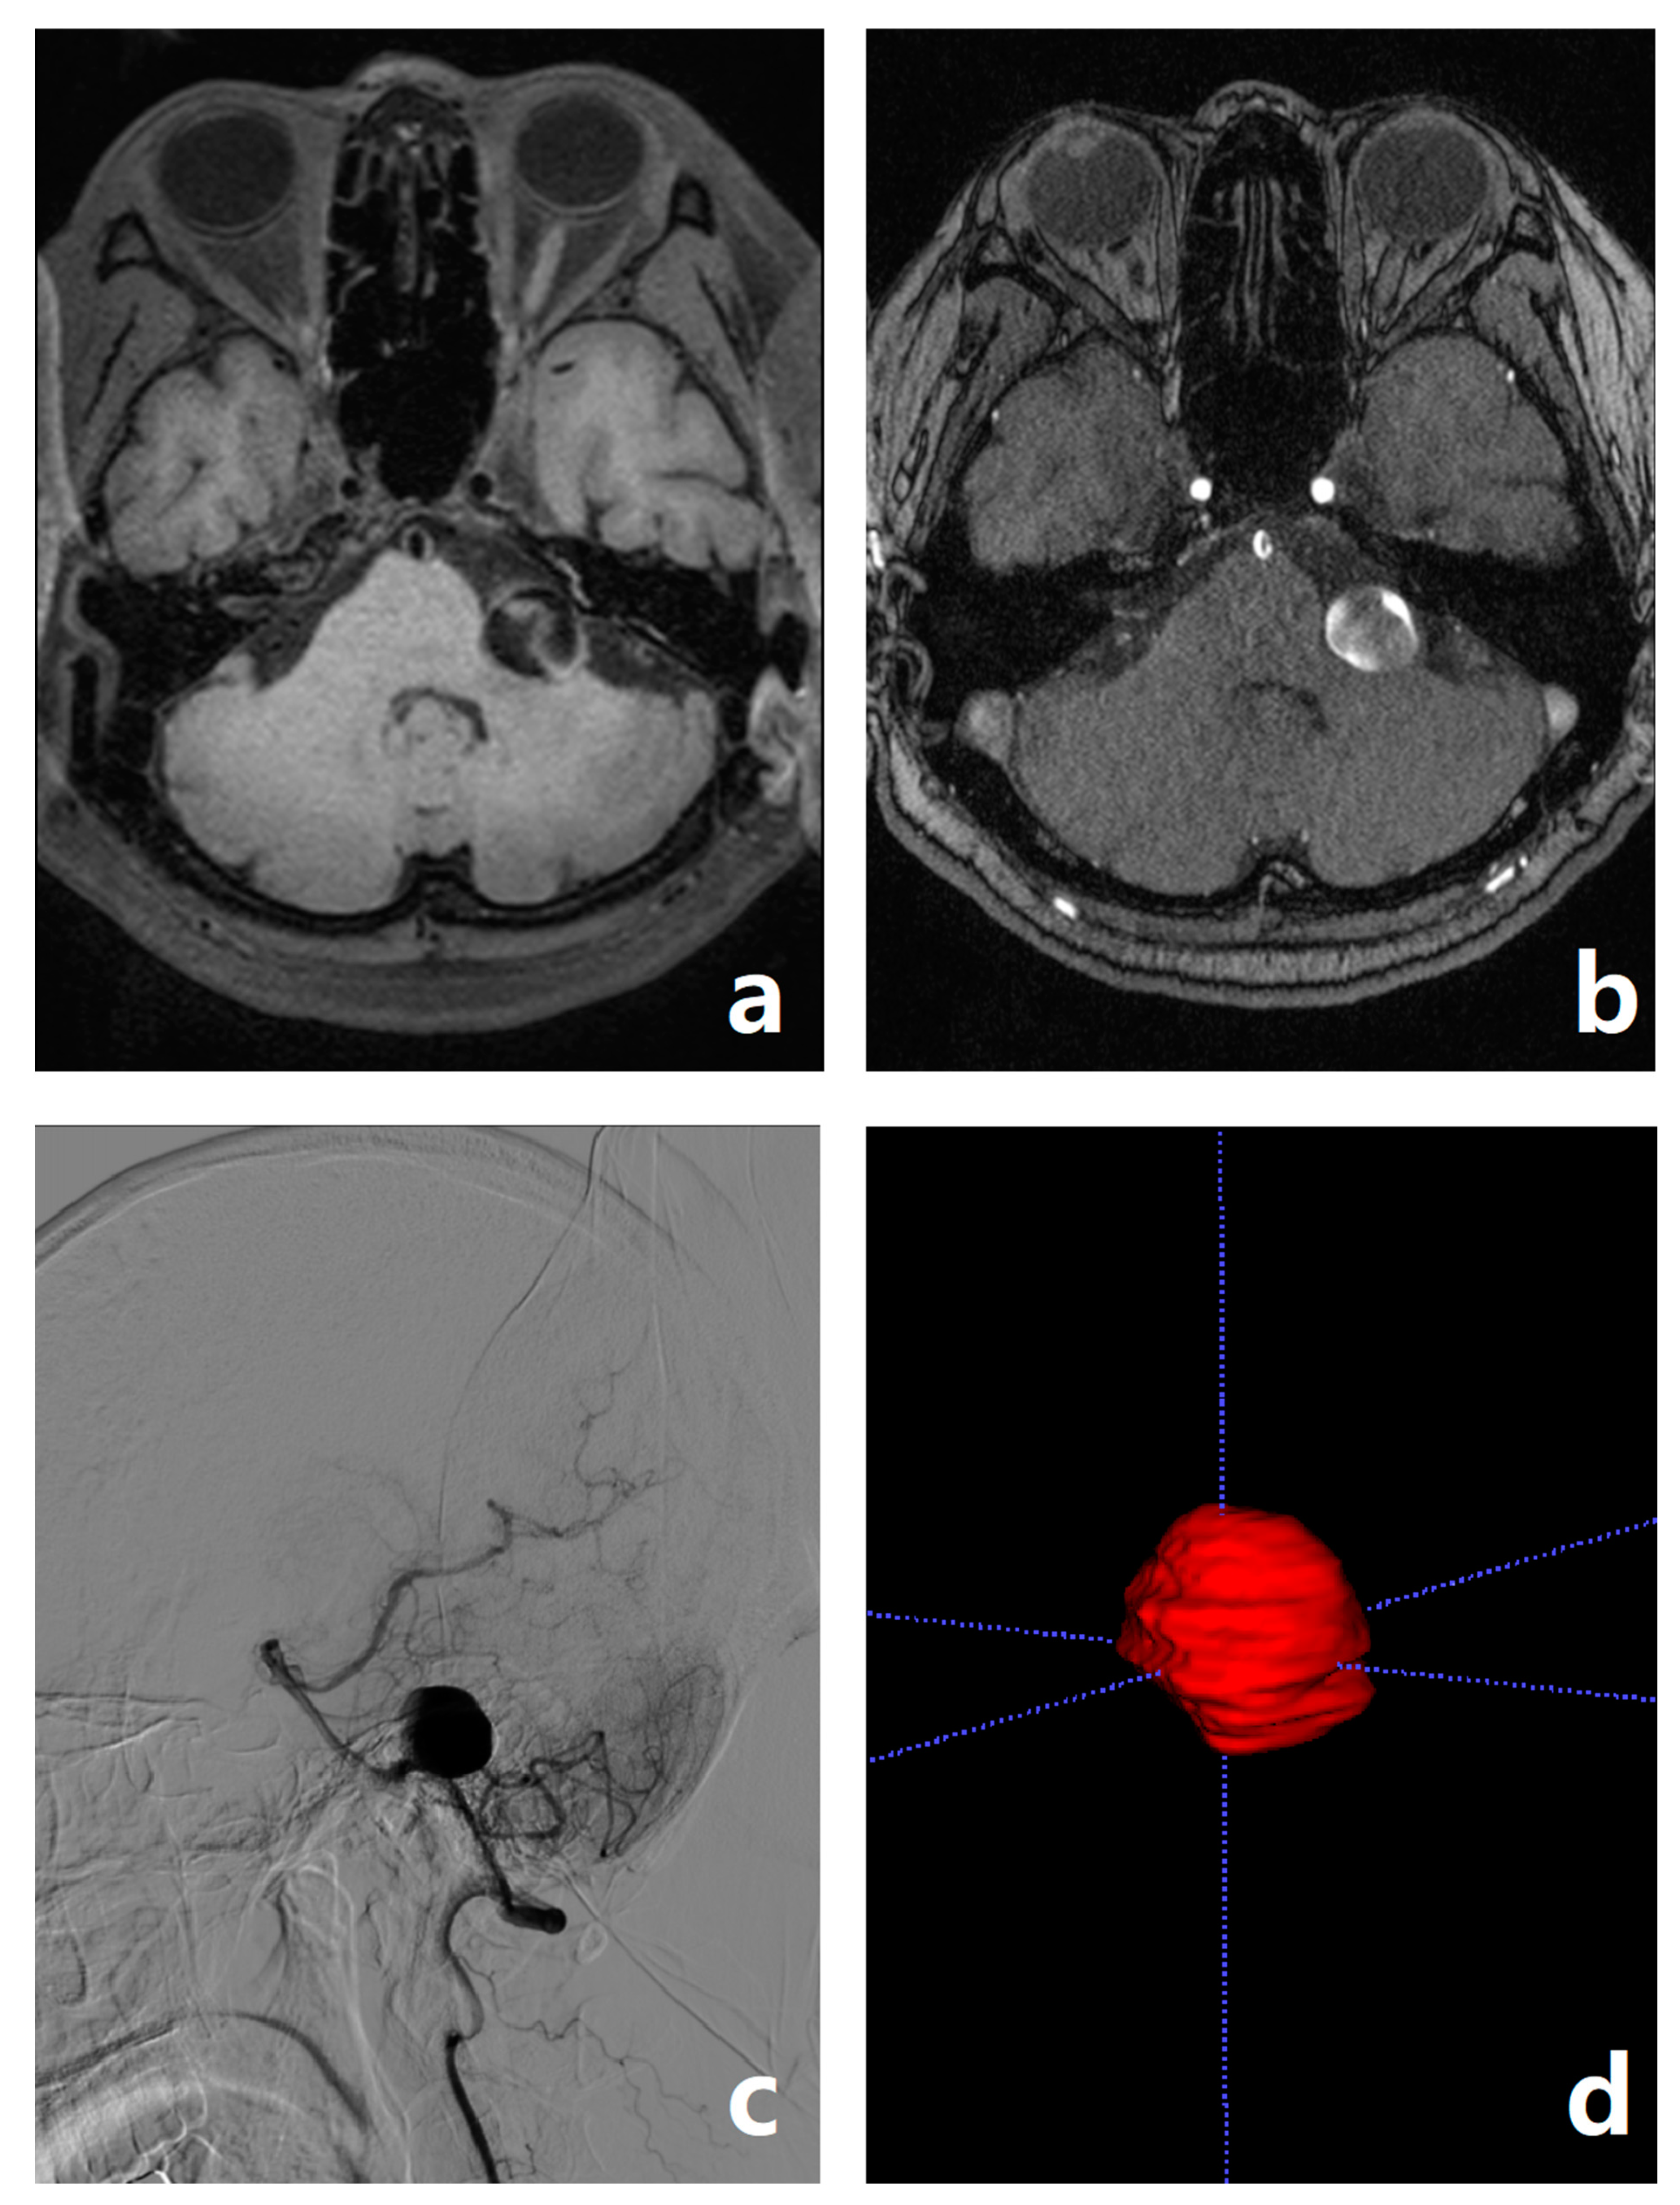

- Wang, Y.; Lou, X.; Li, Y.; Sui, B.; Sun, S.; Li, C.; Jiang, P.; Siddiqui, A.; Yang, X. Imaging investigation of intracranial arterial dissecting aneurysms by using 3 T high-resolution MRI and DSA: From the interventional neuroradiologists’ view. Acta Neurochir. 2014, 156, 515–525. [Google Scholar] [CrossRef] [PubMed]

- Tian, Z.; Chen, J.; Zhang, Y.; Liu, J.; Wang, Y.; Sui, B.; Yang, X. Quantitative analysis of intracranial vertebrobasilar dissecting aneurysm with intramural hematoma after endovascular treatment using 3-T high-resolution magnetic resonance imaging. World Neurosurg. 2017, 108, 236–243. [Google Scholar] [CrossRef]

- Zhang, M.; Ye, G.; Liu, Y.; Wang, Q.; Li, S.; Wang, Y. Clinical application of high-resolution MRI in combination with digital subtraction angiography in the diagnosis of vertebrobasilar artery dissecting aneurysm: An observational study (STROBE compliant). Medicine 2019, 98, e14857. [Google Scholar] [CrossRef] [PubMed]

- Cao, X.; Xia, W.; Tang, Y.; Zhang, B.; Yang, J.M.; Zeng, Y.W.; Geng, D.Y.; Zhang, J. Radiomic model for distinguishing dissecting aneurysms from complicated saccular aneurysms on high-resolution magnetic resonance imaging. J. Stroke Cerebrovasc. Dis. 2020, 29, 105268. [Google Scholar] [CrossRef] [PubMed]